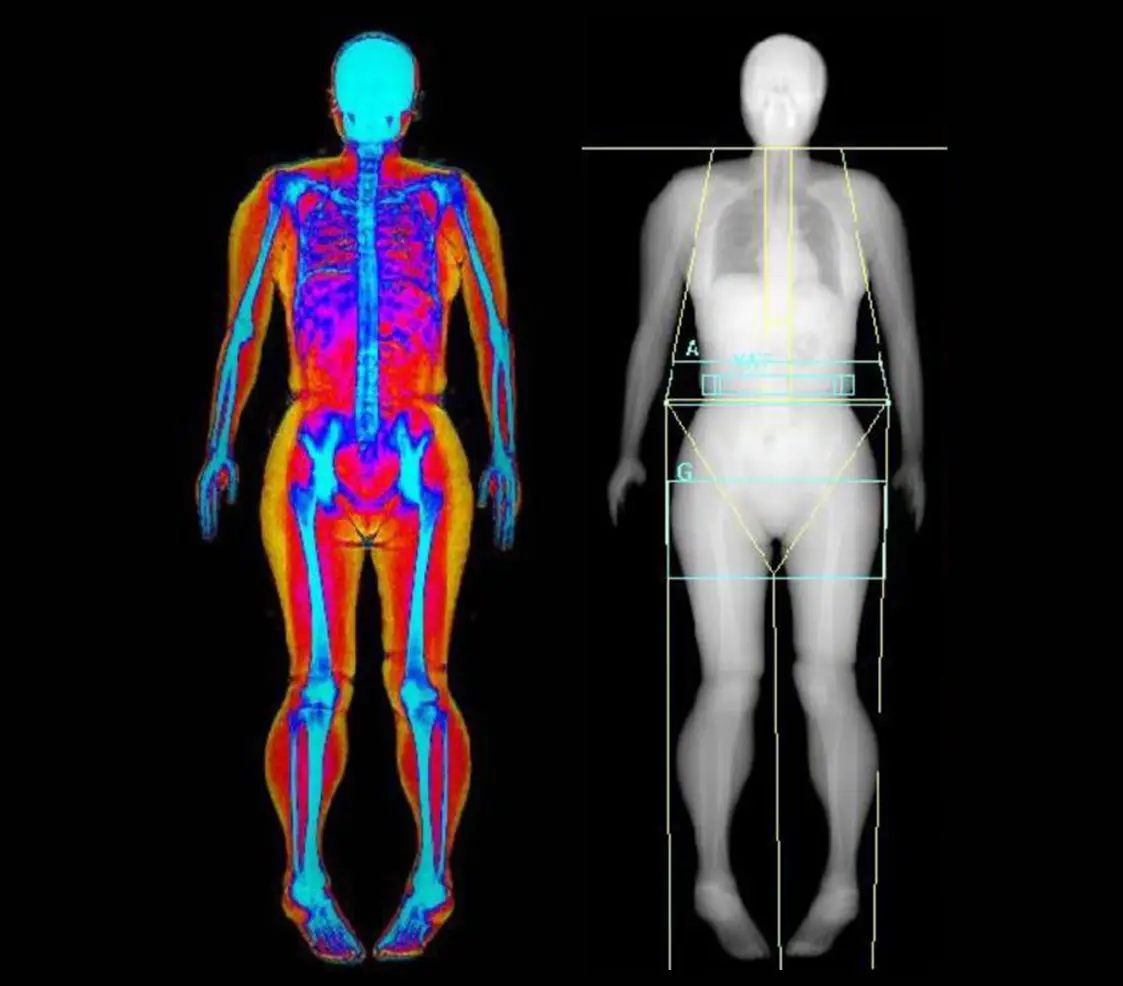

Manuale teorico-pratico essenziale, pensato per i professionisti della salute, del fitness e della nutrizione che desiderano padroneggiare la misurazione e la corretta valutazione dei componenti corporei nell’atleta. Il libro evidenzia come lo studio della composizione corporea sia cruciale per l’ottimizzazione dell’allenamento e delle strategie nutrizionali.

Smetti di affidarti a stime superficiali. Per ottimizzare la performance sportiva e la pianificazione nutrizionale, è indispensabile una misurazione accurata e un’interpretazione scientifica della composizione corporea. Questo manuale è la guida teorico-pratica che colma il divario tra la ricerca accademica e l’applicazione clinica e sul campo. Elevate la qualità della vostra consulenza, trasformando i dati in risultati tangibili per i vostri atleti. Aggiornato sui più recenti studi scientifici internazionali.

La corretta misurazione della composizione corporea non è un’opzione, ma un imperativo per chi opera nello sport. Molti strumenti sono costosi o complessi, ma l’efficacia non deve dipendere solo dalla tecnologia. Il testo si concentra sulle metodiche più affidabili, accessibili ed efficienti per l’ambiente sportivo e clinico: l’Antropometria e l’Analisi dell’Impedenza Bioelettrica (BIA).

Lo studio della composizione corporea si articola attraverso una classificazione gerarchica dei modelli, che spaziano dal livello atomico fino all’analisi del corpo intero. Nonostante la sua semplicità, il modello a due compartimenti (massa grassa e massa magra) rimane il più diffuso in ambito pratico. Ogni strumento di misurazione deve soddisfare rigorosi requisiti di validità metrologica, tra cui accuratezza, precisione e sensibilità. È fondamentale riconoscere variabili intervenienti, come l’idratazione, la densità ossea e la temperatura corporea, poiché possono alterare in modo significativo l’esito delle misurazioni. La conoscenza approfondita dei principi teorici alla base delle metodiche più accessibili, come l’Antropometria e la BIA, è perciò essenziale per interpretare correttamente le variazioni dei compartimenti indotte da specifici regimi di allenamento o interventi nutrizionali.